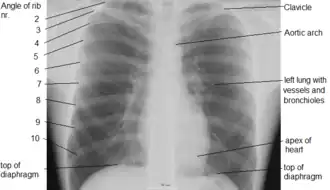

A chest radiograph with the angle parts of the ribs and some other landmarks labeled.

In the average person, the diaphragm should be intersected by the 5th to 7th anterior ribs at the mid-clavicular line, and 9 to 10 posterior ribs should be viewable on a normal PA inspiratory film. An increase in the number of viewable ribs implies hyperinflation, as can occur, for example, with obstructive lung disease or foreign body aspiration. A decrease implies hypoventilation, as can occur with restrictive lung disease, pleural effusions or atelectasis. Underexpansion can also cause interstitial markings due to parenchymal crowding, which can mimic the appearance of interstitial lung disease. Enlargement of the right descending pulmonary artery can indirectly reflect changes of pulmonary hypertension, with a size greater than 16 mm abnormal in men and 15 mm in women.[6]

Appropriate penetration of the film can be assessed by faint visualization of the thoracic spines and lung markings behind the heart. The right diaphragm is usually higher than the left, with the liver being situated beneath it in the abdomen. The minor fissure can sometimes be seen on the right as a thin horizontal line at the level of the fifth or sixth rib. Splaying of the carina can also suggest a tumor or process in the middle mediastinum or enlargement of the left atrium, with a normal angle of approximately 60 degrees. The right paratracheal stripe is also important to assess, as it can reflect a process in the posterior mediastinum, in particular the spine or paraspinal soft tissues; normally it should measure 3 mm or less. The left paratracheal stripe is more variable and only seen in 25% of normal patients on posteroanterior views.[7]

Localization of lesions or inflammatory and infectious processes can be difficult to discern on chest radiograph, but can be inferred by silhouetting and the hilum overlay sign with adjacent structures. If either hemidiaphragm is blurred, for example, this suggests the lesion to be from the corresponding lower lobe. If the right heart border is blurred, than the pathology is likely in the right middle lobe, though a cavum deformity can also blur the right heard border due to indentation of the adjacent sternum. If the left heart border is blurred, this implies a process at the lingula.[8]